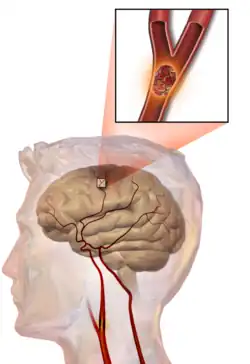

Embolic stroke

An embolic stroke refers to an arterial embolism (a blockage of an artery) by an embolus, a traveling particle or debris in the arterial bloodstream originating from elsewhere. An embolus is most frequently a thrombus, but it can also be a number of other substances including fat (e.g., from bone marrow in a broken bone), air, cancer cells or clumps of bacteria (usually from infectious endocarditis).[54]

Because an embolus arises from elsewhere, local therapy solves the problem only temporarily. Thus, the source of the embolus must be identified. Because the embolic blockage is sudden in onset, symptoms are usually maximal at the start. Also, symptoms may be transient as the embolus is partially resorbed and moves to a different location or dissipates altogether.

Emboli most commonly arise from the heart (especially in atrial fibrillation) but may originate from elsewhere in the arterial tree. In paradoxical embolism, a deep vein thrombosis embolizes through an atrial or ventricular septal defect in the heart into the brain.[54]